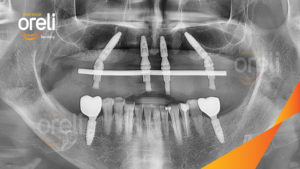

Trồng răng Implant mất răng toàn hàm tại Oreli

Nếu bạn bị thiếu tất cả các răng, nha khoa cấy ghép từ Nha khoa Oreli là lựa chọn tối ưu để khôi phục miệng của bạn với đầy đủ chức năng.

Cấy ghép nha khoa là tiêu chuẩn chăm sóc thay thế răng hiện đại cho dù đó là một răng hay tất cả các răng của bạn.